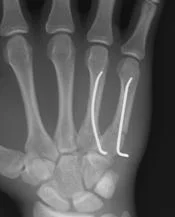

Metacarpal Fractures

- Careful about rotational malalignment

- Check rotation by flexing the fingers

- Undisplaced / or only one MC

- Treatment by cast / or splint

- Displaced / Rotated / Multiple

- Treated by internal fixation (screws / plates / wires)